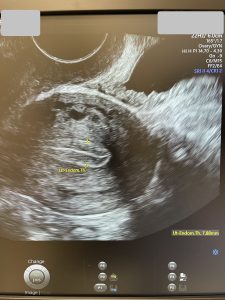

La momentul în care scriu aceste rânduri, am făcut deja și a treia stimulare, am obținut 16 ovocite și 6 blastociști. Toți au fost testați PGT-A și așteptăm să vină rezultatul testării…